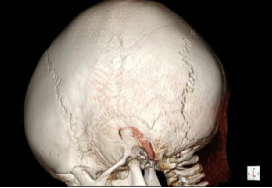

接诊后,医疗团队为凯凯进行了详尽的检查。入院查体显示,凯凯头围50厘米,头颅外观呈现特征性的前后径较长,前额部隆起,触诊可及矢状缝、冠状缝及颞鳞缝区域骨质硬化,失去了正常婴儿颅缝应有的弹性与间隙。结合外院头颅CT三维重建结果——清晰显示冠状缝、矢状缝、颞鳞缝过早闭合,并伴有额骨前突——诊断明确:多颅缝早闭,亦即狭颅症。

术前